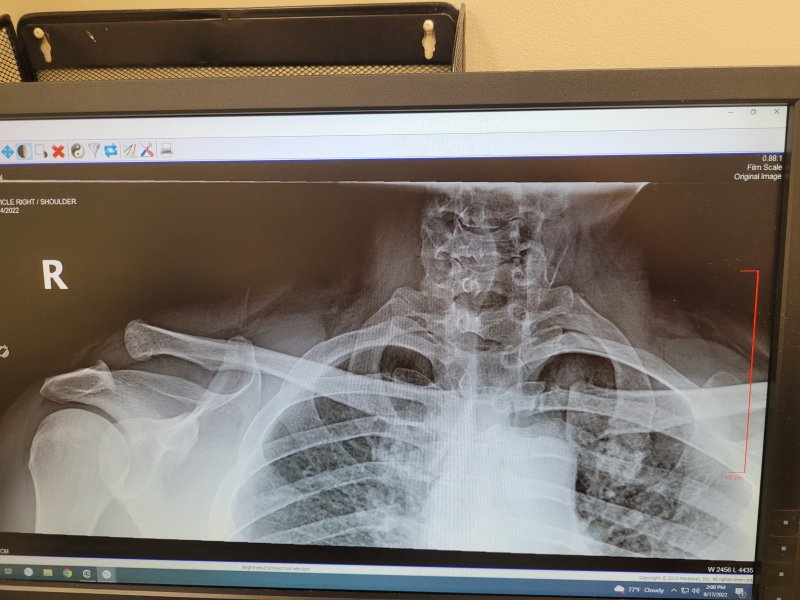

I've got one too, class 2. Was told PT would stave off most of the downsides, and surgery wasn't really necessary, unless I landed hard on it again. Any muscle damage, or just the ligament?

On the plus side, I can freak people out if I relax my shoulder muscles.

No muscle damage and no breaks. They said PT could return most of my mobility but I wouldn't get all my strength back and the collar bone would always stick above my shoulder. He also said with this kind of tear, 90% of those who opt for PT come back months later for the surgery because they're not happy with the results. Surgery please.